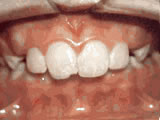

Phase-One

Patient’s parents were concerned about both aesthetics and the health of the erupting permanent teeth when they brought him to the orthodontist at age eight. The lower front teeth were crowded and touching the palate, and the upper front teeth were extremely displaced from their normal positions. After 12 months of Phase-One treatment with an expander and partial braces, patient’s appearance and dental function were vastly improved.